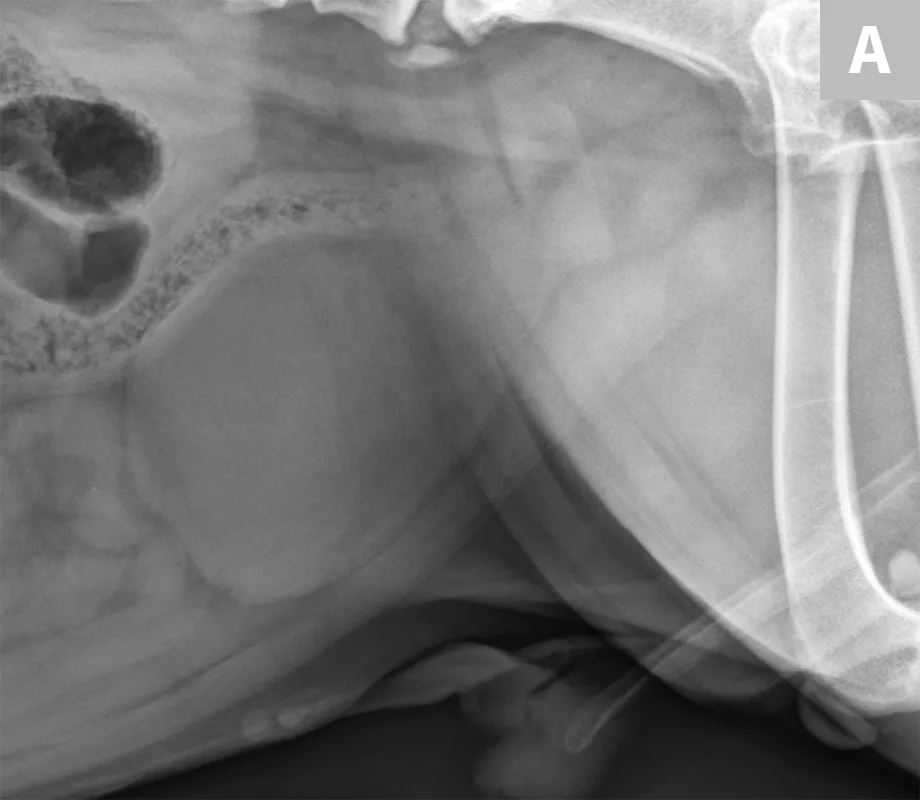

Differentiation between a complete vs partial ureteral obstruction can be difficult with survey radiography and ultrasonography alone. Antegrade pyelography (nephropyelocentesis with renal pelvic injection of iodinated positive contrast medium using ultrasound guidance) may be useful for documenting a complete vs partial obstruction (Figure 7).11

FIGURE 7A

1 / 3

Lateral abdominal radiograph of a cat with multiple, small, oval mineral opacities superimposed over the ventral aspect of the retroperitoneal space (arrows). These mineral opacities are arranged linearly extending from the caudal aspect of the kidneys to the level of the urinary bladder.

Antegrade pyelography is beneficial when compared with standard IV urography, as it lowers the risk of potential contrast-induced renal damage and provides excellent filling of the renal collecting system, regardless of renal function.11